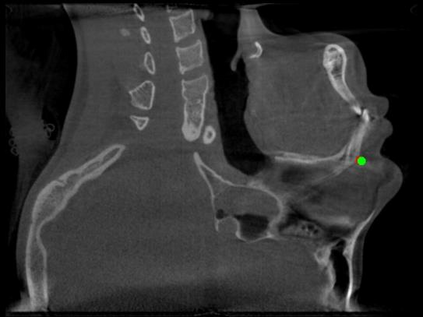

Detecting 3D landmarks on cone-beam computed tomography (CBCT) is crucial to assessing and quantifying the anatomical abnormalities in 3D cephalometric analysis. However, the current methods are time-consuming and suffer from large biases in landmark localization, leading to unreliable diagnosis results. In this work, we propose a novel Structure-Aware Long Short-Term Memory framework (SA-LSTM) for efficient and accurate 3D landmark detection. To reduce the computational burden, SA-LSTM is designed in two stages. It first locates the coarse landmarks via heatmap regression on a down-sampled CBCT volume and then progressively refines landmarks by attentive offset regression using multi-resolution cropped patches. To boost accuracy, SA-LSTM captures global-local dependence among the cropping patches via self-attention. Specifically, a novel graph attention module implicitly encodes the landmark's global structure to rationalize the predicted position. Moreover, a novel attention-gated module recursively filters irrelevant local features and maintains high-confident local predictions for aggregating the final result. Experiments conducted on an in-house dataset and a public dataset show that our method outperforms state-of-the-art methods, achieving 1.64 mm and 2.37 mm average errors, respectively. Furthermore, our method is very efficient, taking only 0.5 seconds for inferring the whole CBCT volume of resolution 768$\times$768$\times$576.